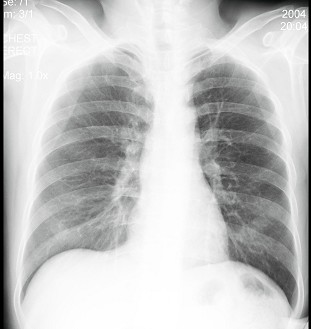

男性患者,38岁,突感胸部不适,X线检查如图,最可能的诊断是 ( ) 1JZ-03951.jpg 1JZ-03952.jpg

• A.肺部炎症

• B.胸腔积液

• C.肺结核

• D.正常心、肺、膈

• E.气胸